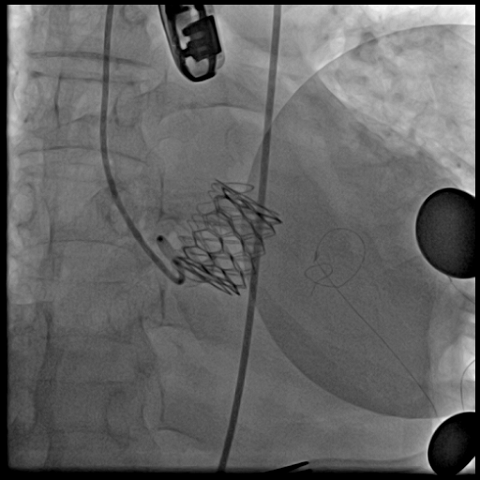

术前经详尽评估患者病情,通过CT重建观察到既往植入的自膨式TAVR瓣膜呈椭圆形,测量瓣环直径,及双侧冠脉开口高度,并评估外周血管入路。由于患者外周血管钙化严重且迂曲,经外周血管途径有较大风险,决定对该病例采用经心尖途径行TAVR瓣膜内 “瓣中瓣”手术。但第二次经心尖途径又将面临心脏、肺、胸壁肌肉组织的粘连,手术难度大。经术前反复讨论和仔细测量毁损TAVR瓣膜的平均内径和冠脉开口高度,决定选用25号 Renato球扩瓣膜。Renato球扩式瓣中瓣可以提供更强的径向支撑力,瓣架高度低,术前模拟植入评估显示冠脉梗阻风险低。手术过程顺利,最终瓣中瓣植入位置理想,功能表现出色,主动脉根部造影及经食道超声观察无瓣中及瓣周返流。

球扩瓣中瓣

瓣中瓣植入后主动脉根部造影